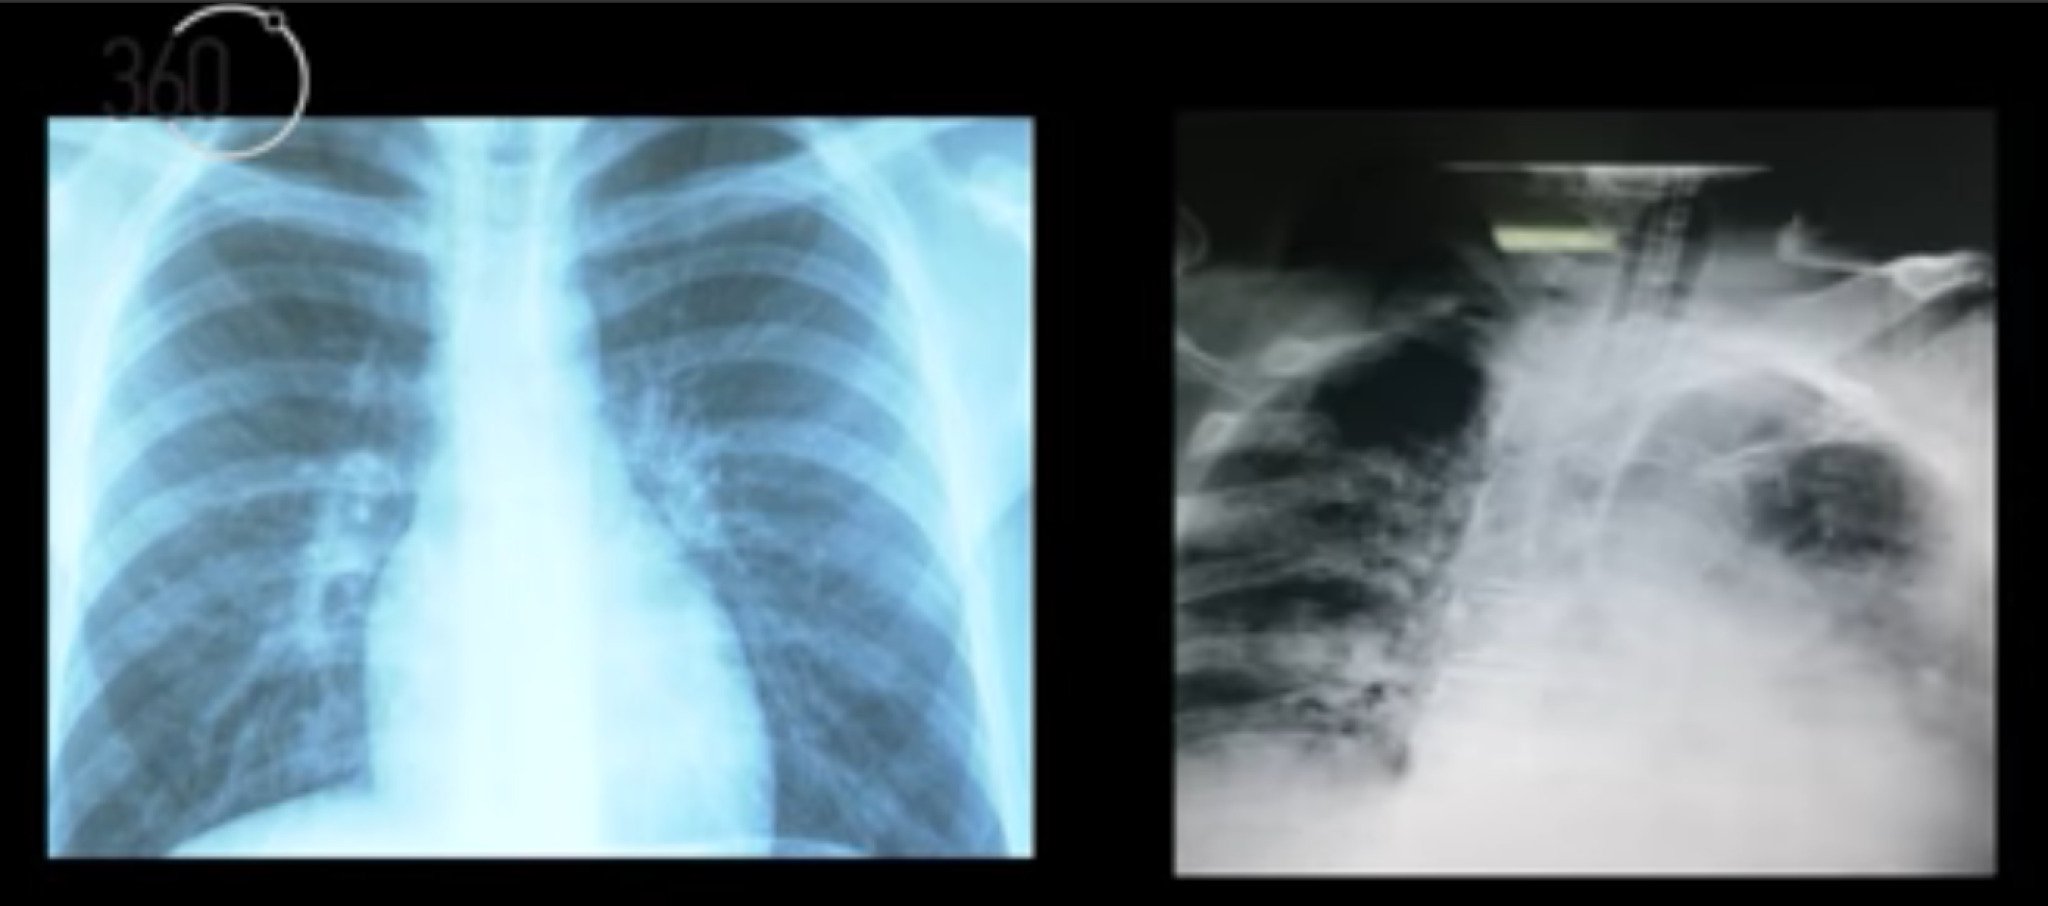

beli-drobovi

(ВИДЕО) Дишат како низ срчи – снимки од бели дробови на македонски пациенти со ковид-19